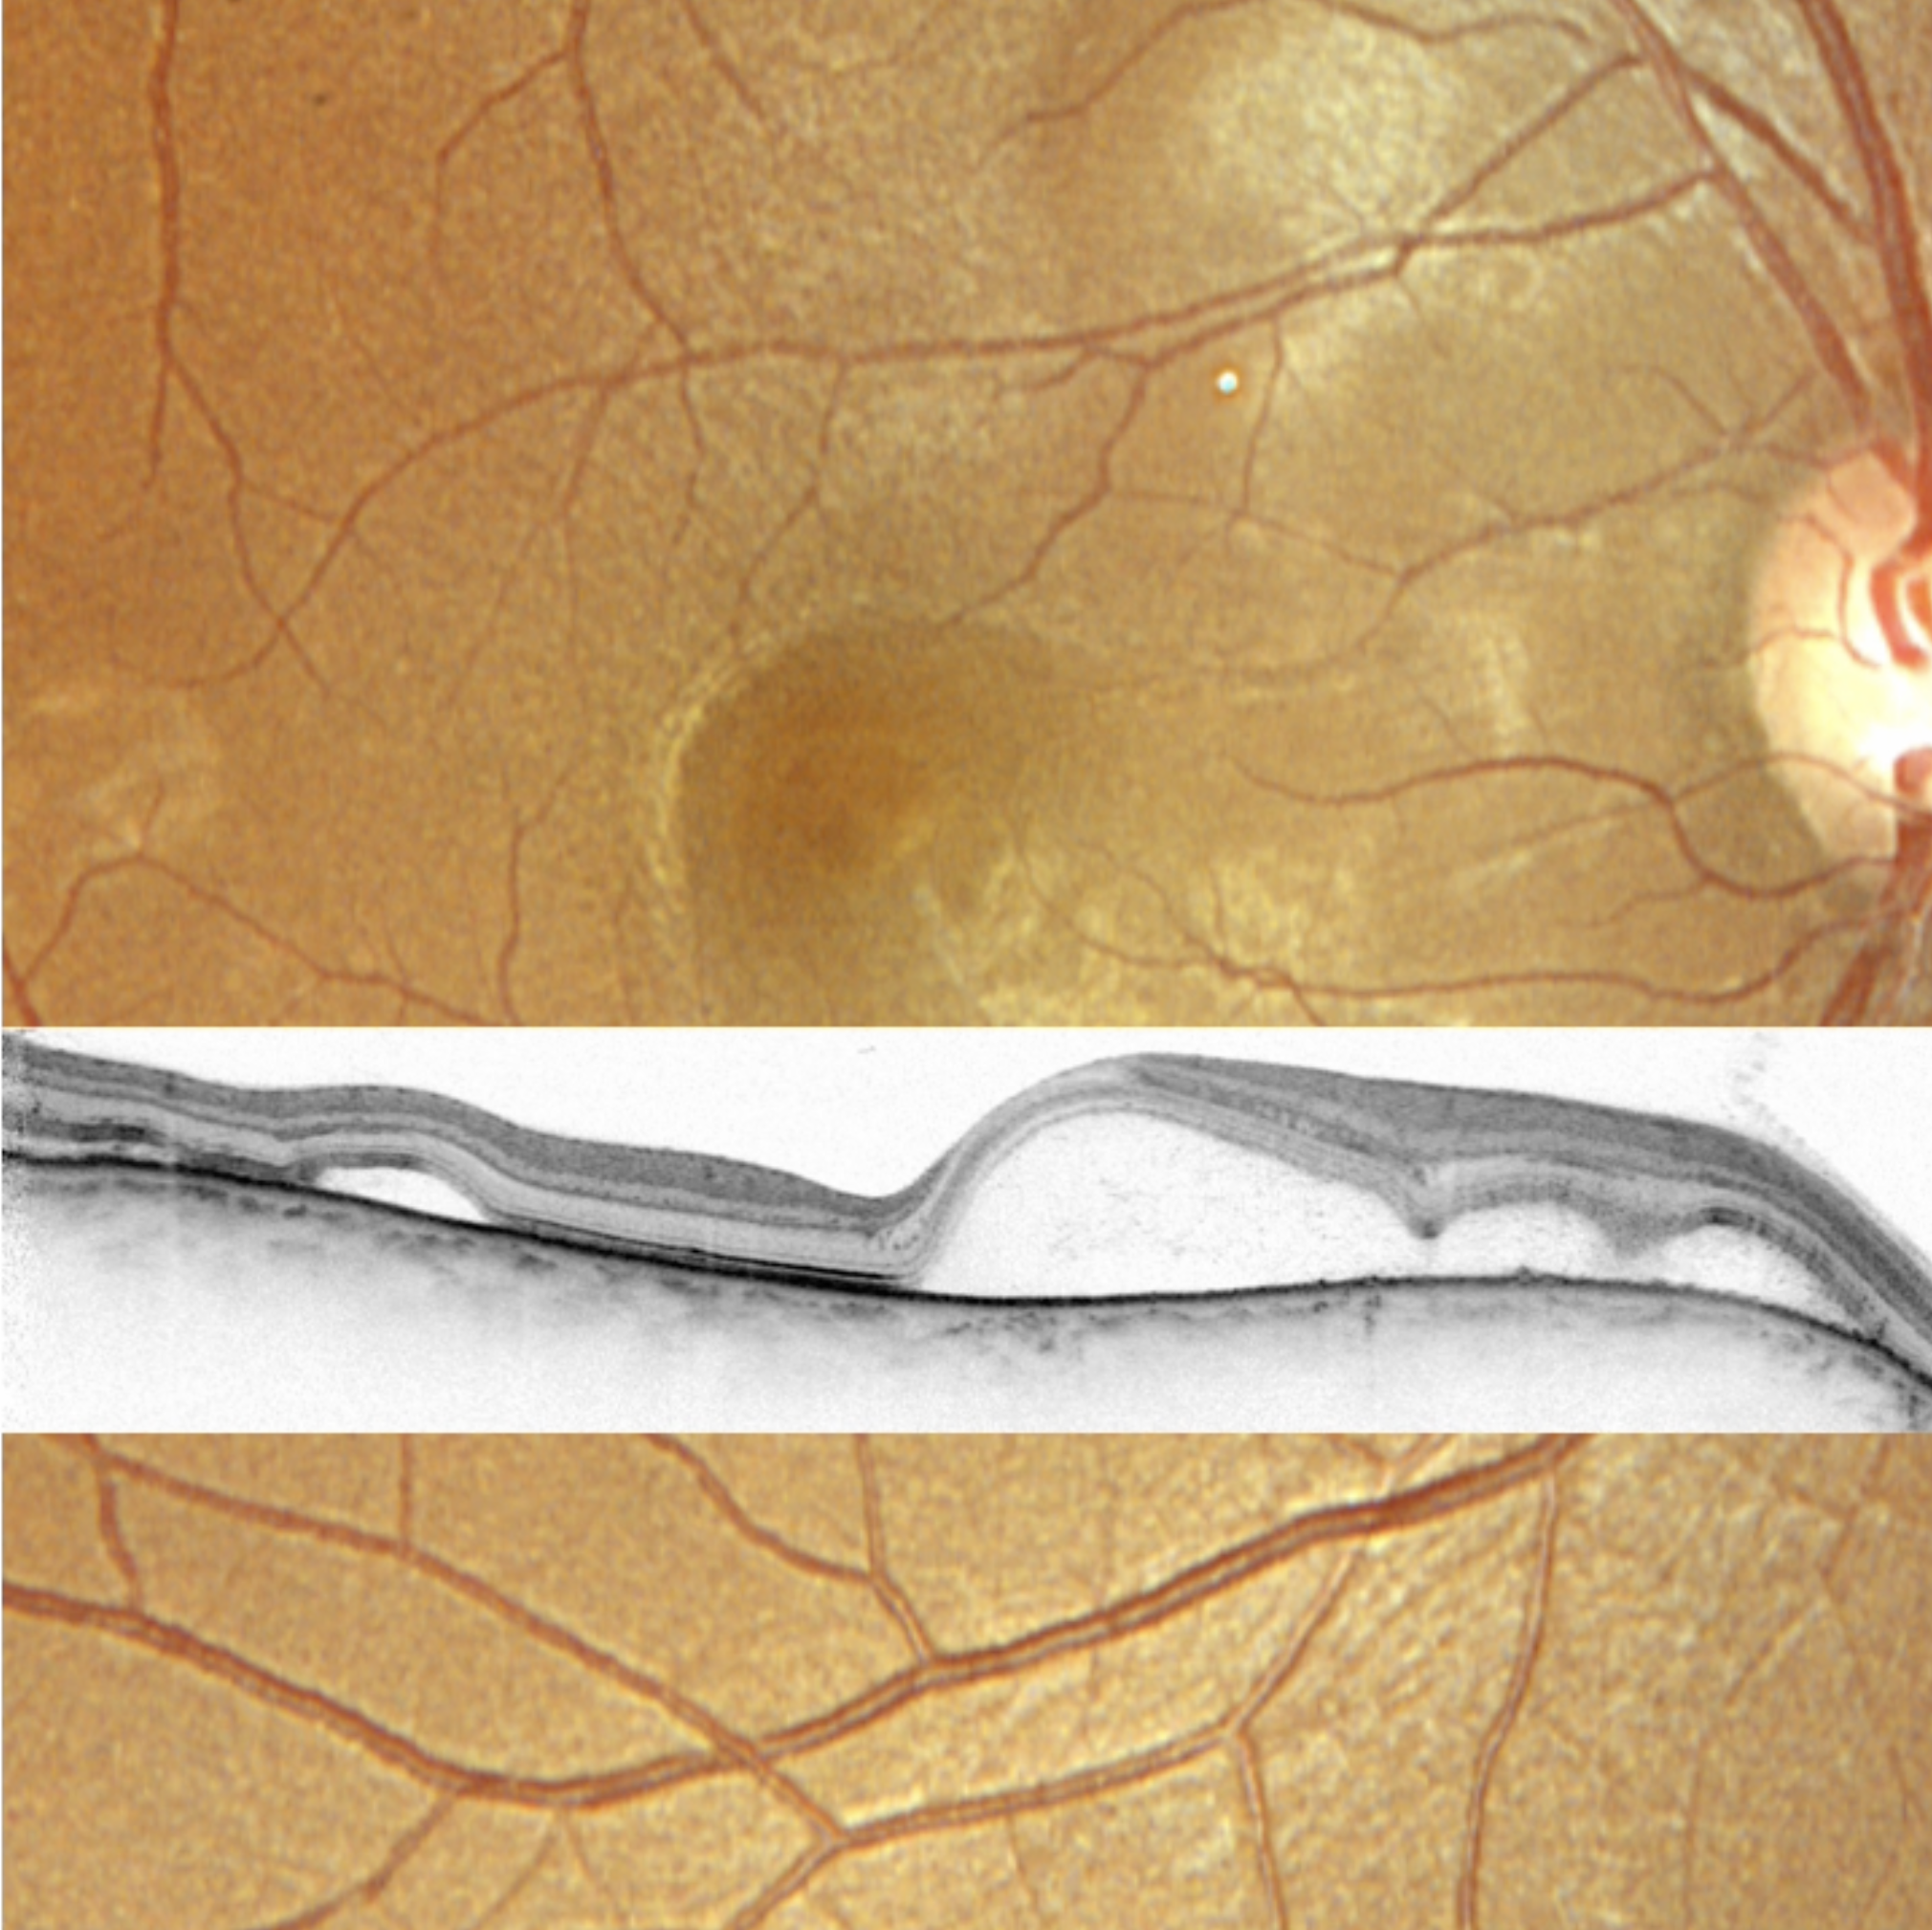

Rétinoschisis bulleux temporal supérieur de l’œil droit

Baisse d’acuité visuelle soudaine de l’œil droit, à 0.05, chez une femme de 38 ans, sans facteur déclenchant retrouvé.